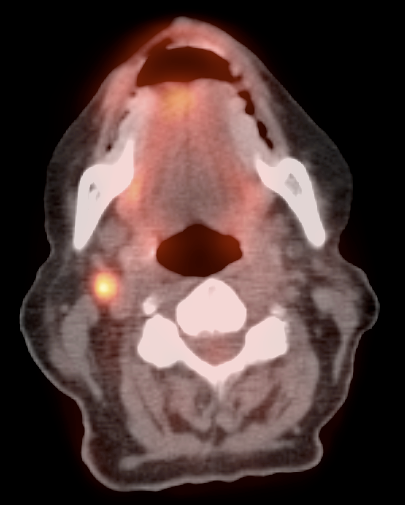

• Valuable diagnostic tool for locally advanced disease, to determine nodal status and potential distant metastatic disease (if no evidence of regional or distant disease, initial management is surgical).

• PET/CT has high sensitivity (>80%) and high specificity (>90%) for metastatic lymph nodes ≥ 8.0 mm.

• Lymphatic spread to pelvic and retroperitoneal lymph nodes.

• Hematogenous spread, often to lungs, liver, and bone.